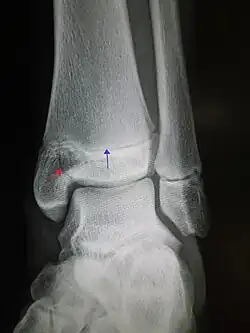

Fracturas del tobillo

Consiste en la rotura de alguno de los huesos que componen la articulación.